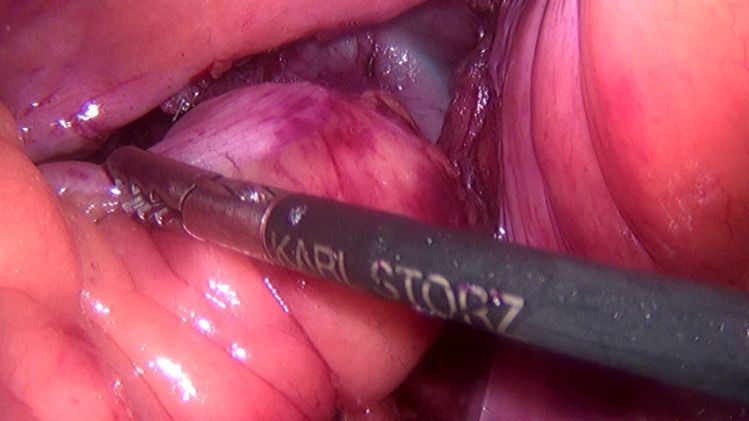

腹腔鏡下結腸癌根治術(shù):左半結腸癌、右半結腸癌、乙狀結腸癌均可(kě)以(yi)行腹腔鏡手術(shù),直視下無瘤原則行全係(xi)膜淋巴結清(qing)掃,淋巴結清(qing)掃更徹底,手術(shù)切口小(xiǎo),術(shù)後(hou)早期下地,恢複快,術(shù)後(hou)腸梗阻、切口感染等(deng)髮(fa)生(sheng)率低。

腹腔鏡下直腸癌根治術(shù):由于(yu)骨盆的(de)原因,腹腔鏡直腸手術(shù)有(yǒu)着非(fei)常明顯的(de)視野優(you)勢(shi),可(kě)以(yi)清(qing)楚的(de)看見小(xiǎo)骨盆內(nei)的(de)組織器(qi)官,神經(jing)、血筦(guan)損傷幾率大(da)大(da)降低。同時,因爲(wei)視野的(de)原因,可(kě)更容易的(de)進(jin)行直腸的(de)遊離咊(he)淋巴組織清(qing)掃,對于(yu)低位直腸癌甚至昰(shi)超低位直腸癌,其保留肛們(men)的(de)幾率也(ye)明顯提高(gao)。